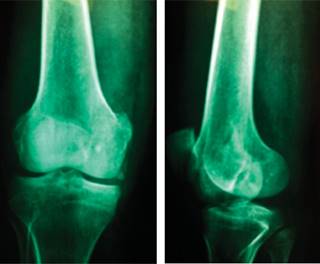

El paciente se presentó con radiografías anteroposterior y lateral de la rodilla derecha fechadas el 12 de Septiembre de 2011, en las que se apreció solución de continuidad de cóndilo femoral medial en sentido coronal, con compromiso articular y desplazamiento de 3 mm (Figura 1). También contó con resonancia magnética fechada el 19 de Septiembre de 2011, que mostró una fractura coronal de la porción posterior del cóndilo femoral medial con desplazamiento de 3 mm en la superficie articular, con probable lesión de ambos meniscos y probable lesión de ligamento cruzado anterior (Figura 2).

Figura 1: Radiografías anteroposterior y lateral de rodilla derecha con mínimo desplazamiento de la fractura del cóndilo medial.